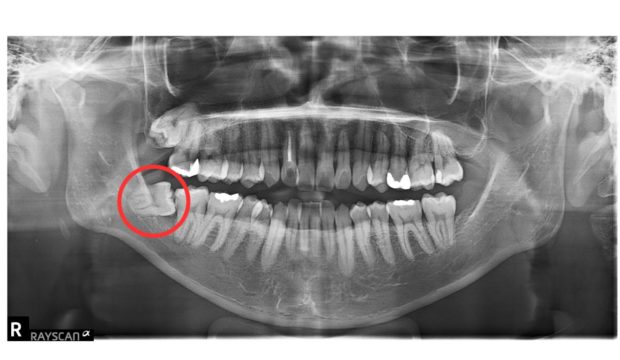

術後2年半